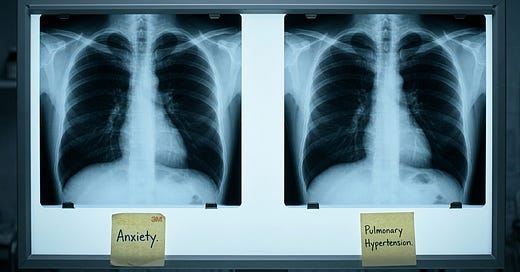

The working diagnosis was anxiety.

Her pulmonary artery pressures were severely elevated. She had pulmonary arterial hypertension.